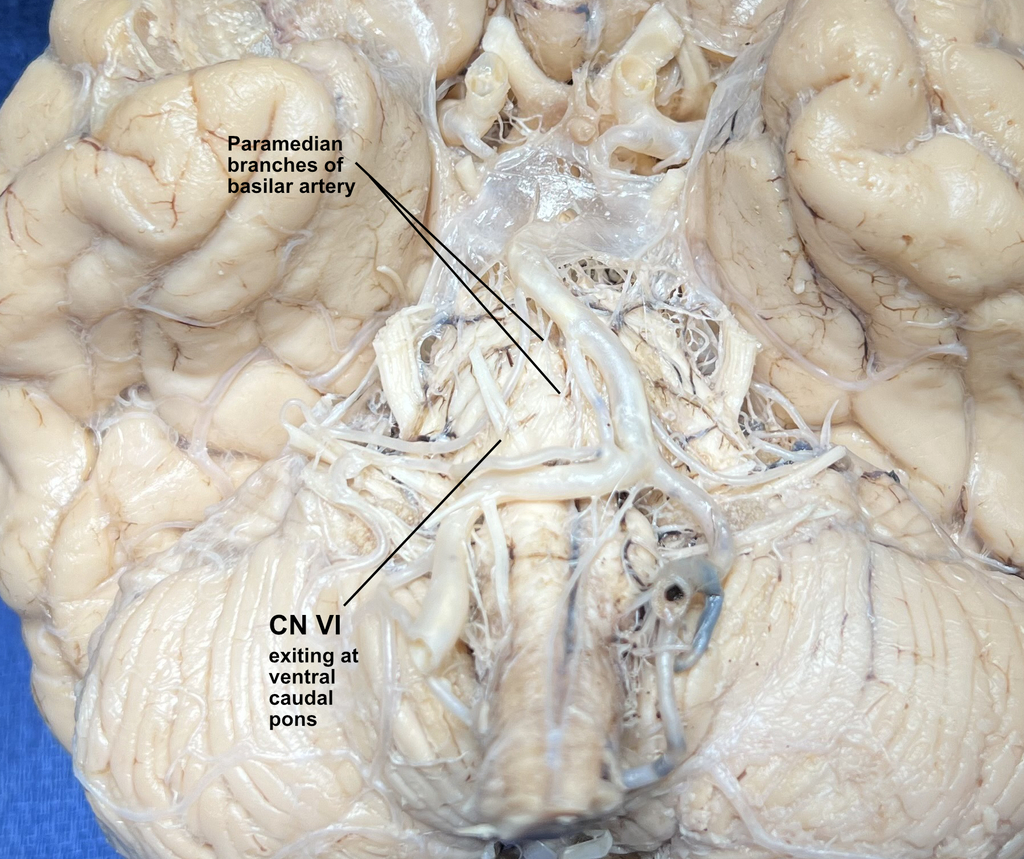

You're on the right track in that CN VI, abducens, is one of the three nerve that innervate the eye muscles, however CN VI innervates the lateral rectus and abducens palsies are horizontal palsies–the eye is only abnormally positioned on the horizontal plane. When, during the H-test, did the eye not function normally. Was it during horizontal movement or vertical? This image shows the vessels whose occlusion would injure the abducens where it exits from the ventral caudal pons: paramedian branches of the basilar artery. Select another nerve that might be more appropriate.